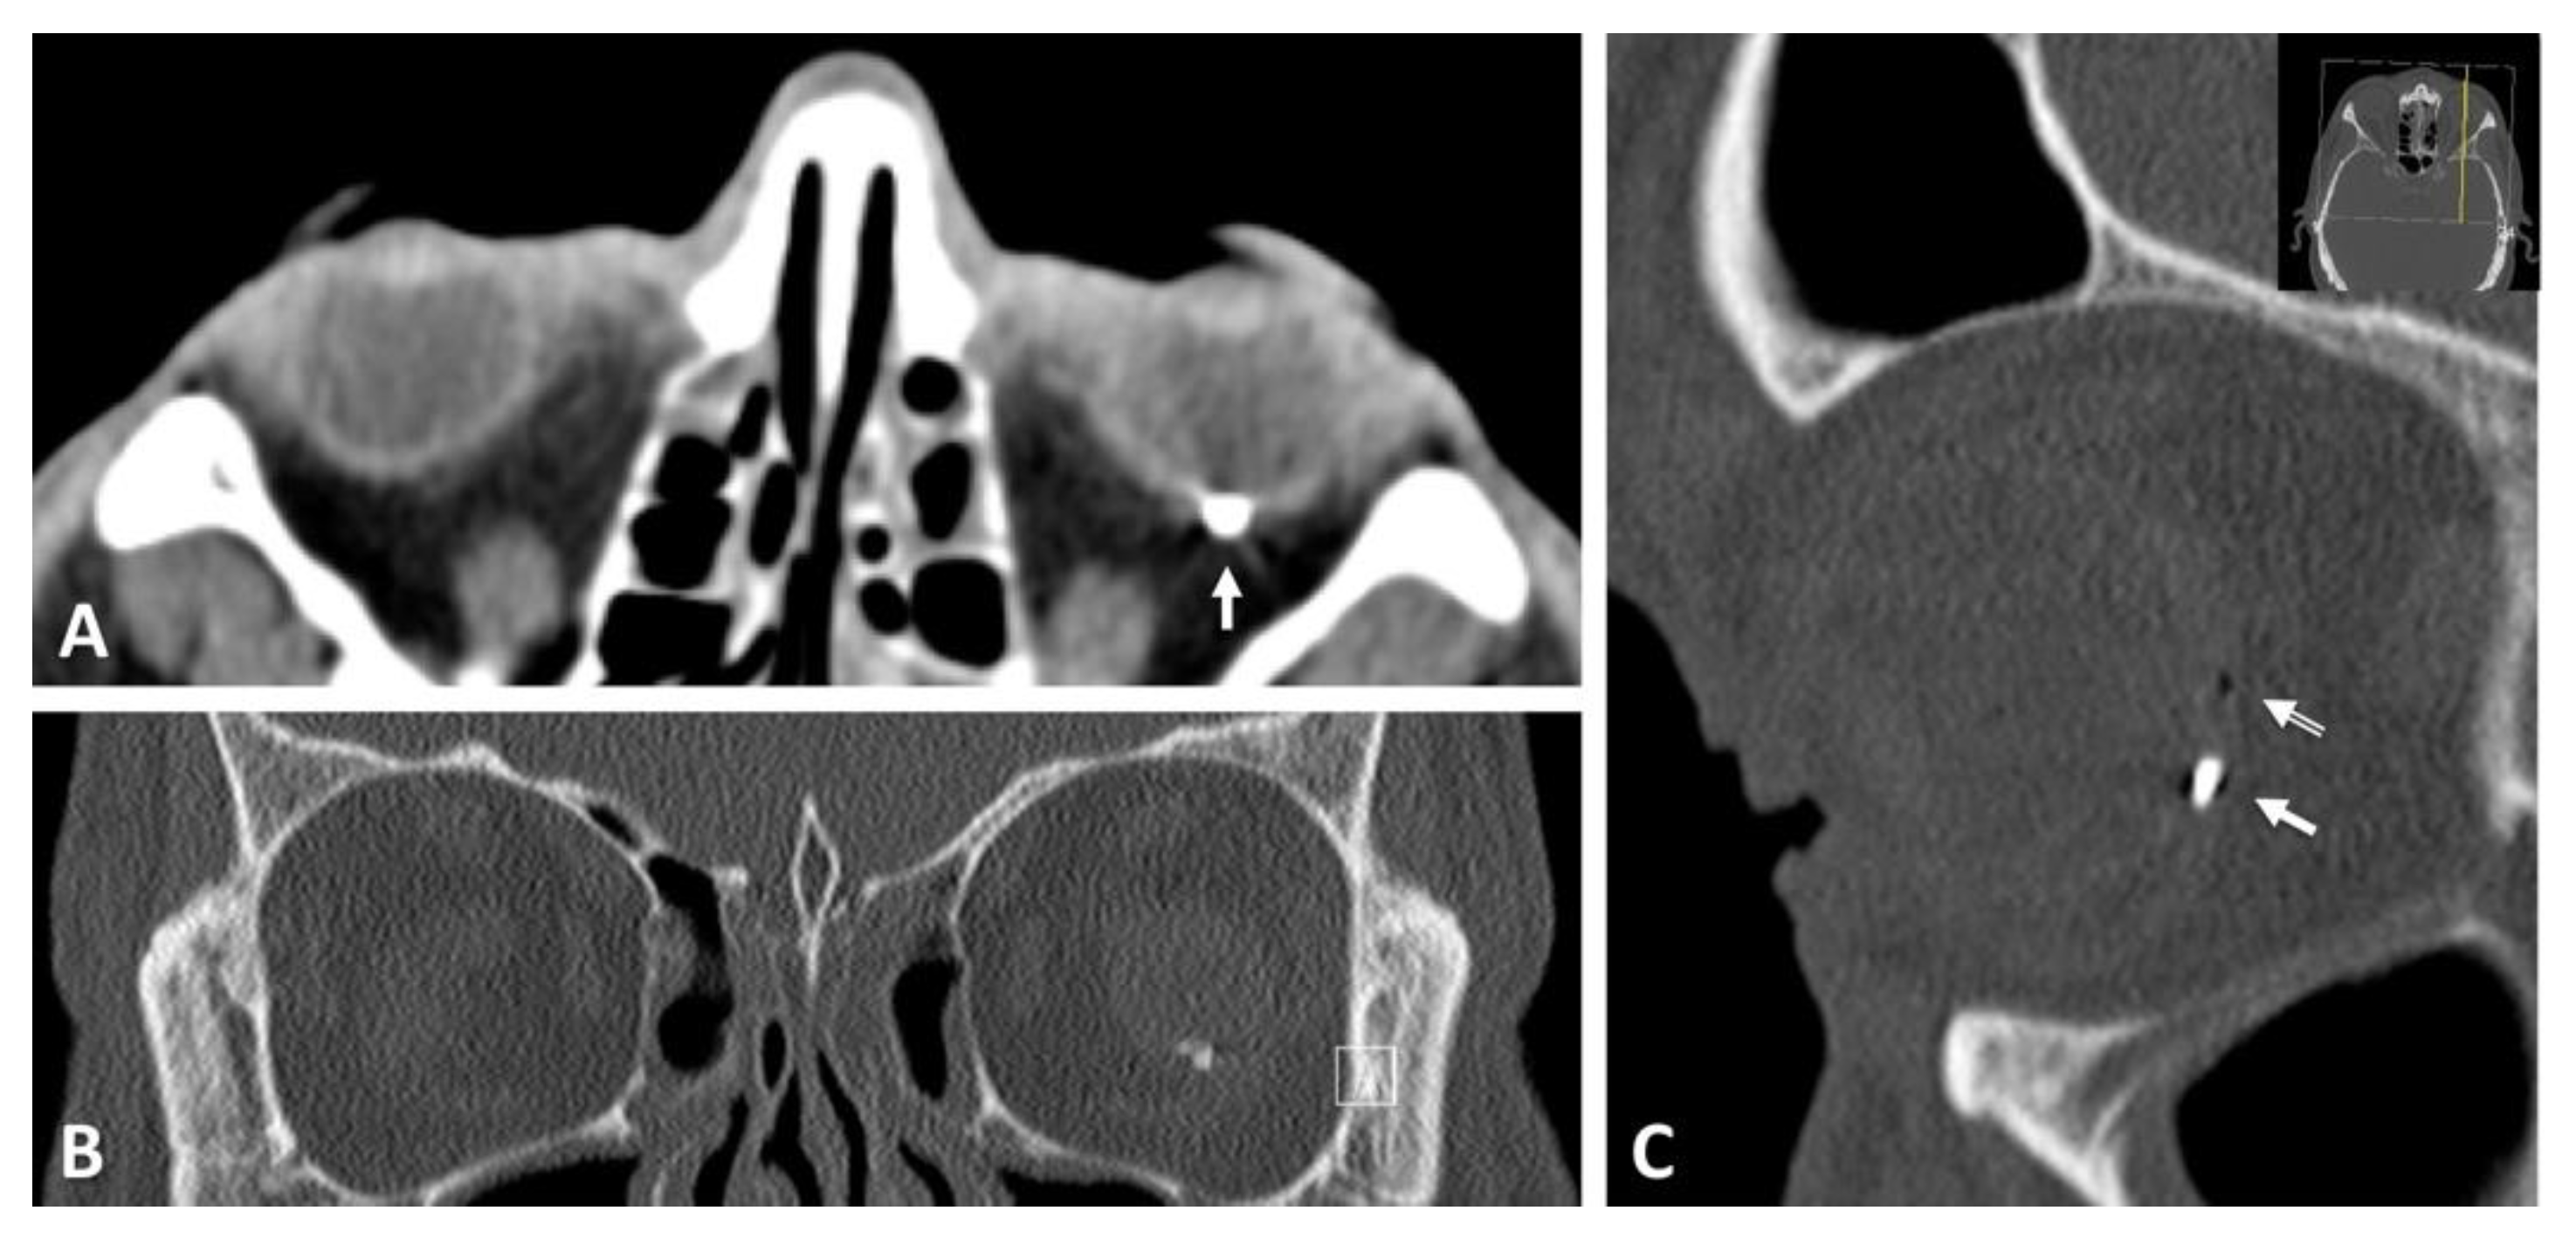

Figure 5. Computed tomographic images from the same patient mentioned in Figure 4. Frontal (A), axial (B) and sagittal (C) images, location of the metallic foreign body at the posterior pole (white arrow).